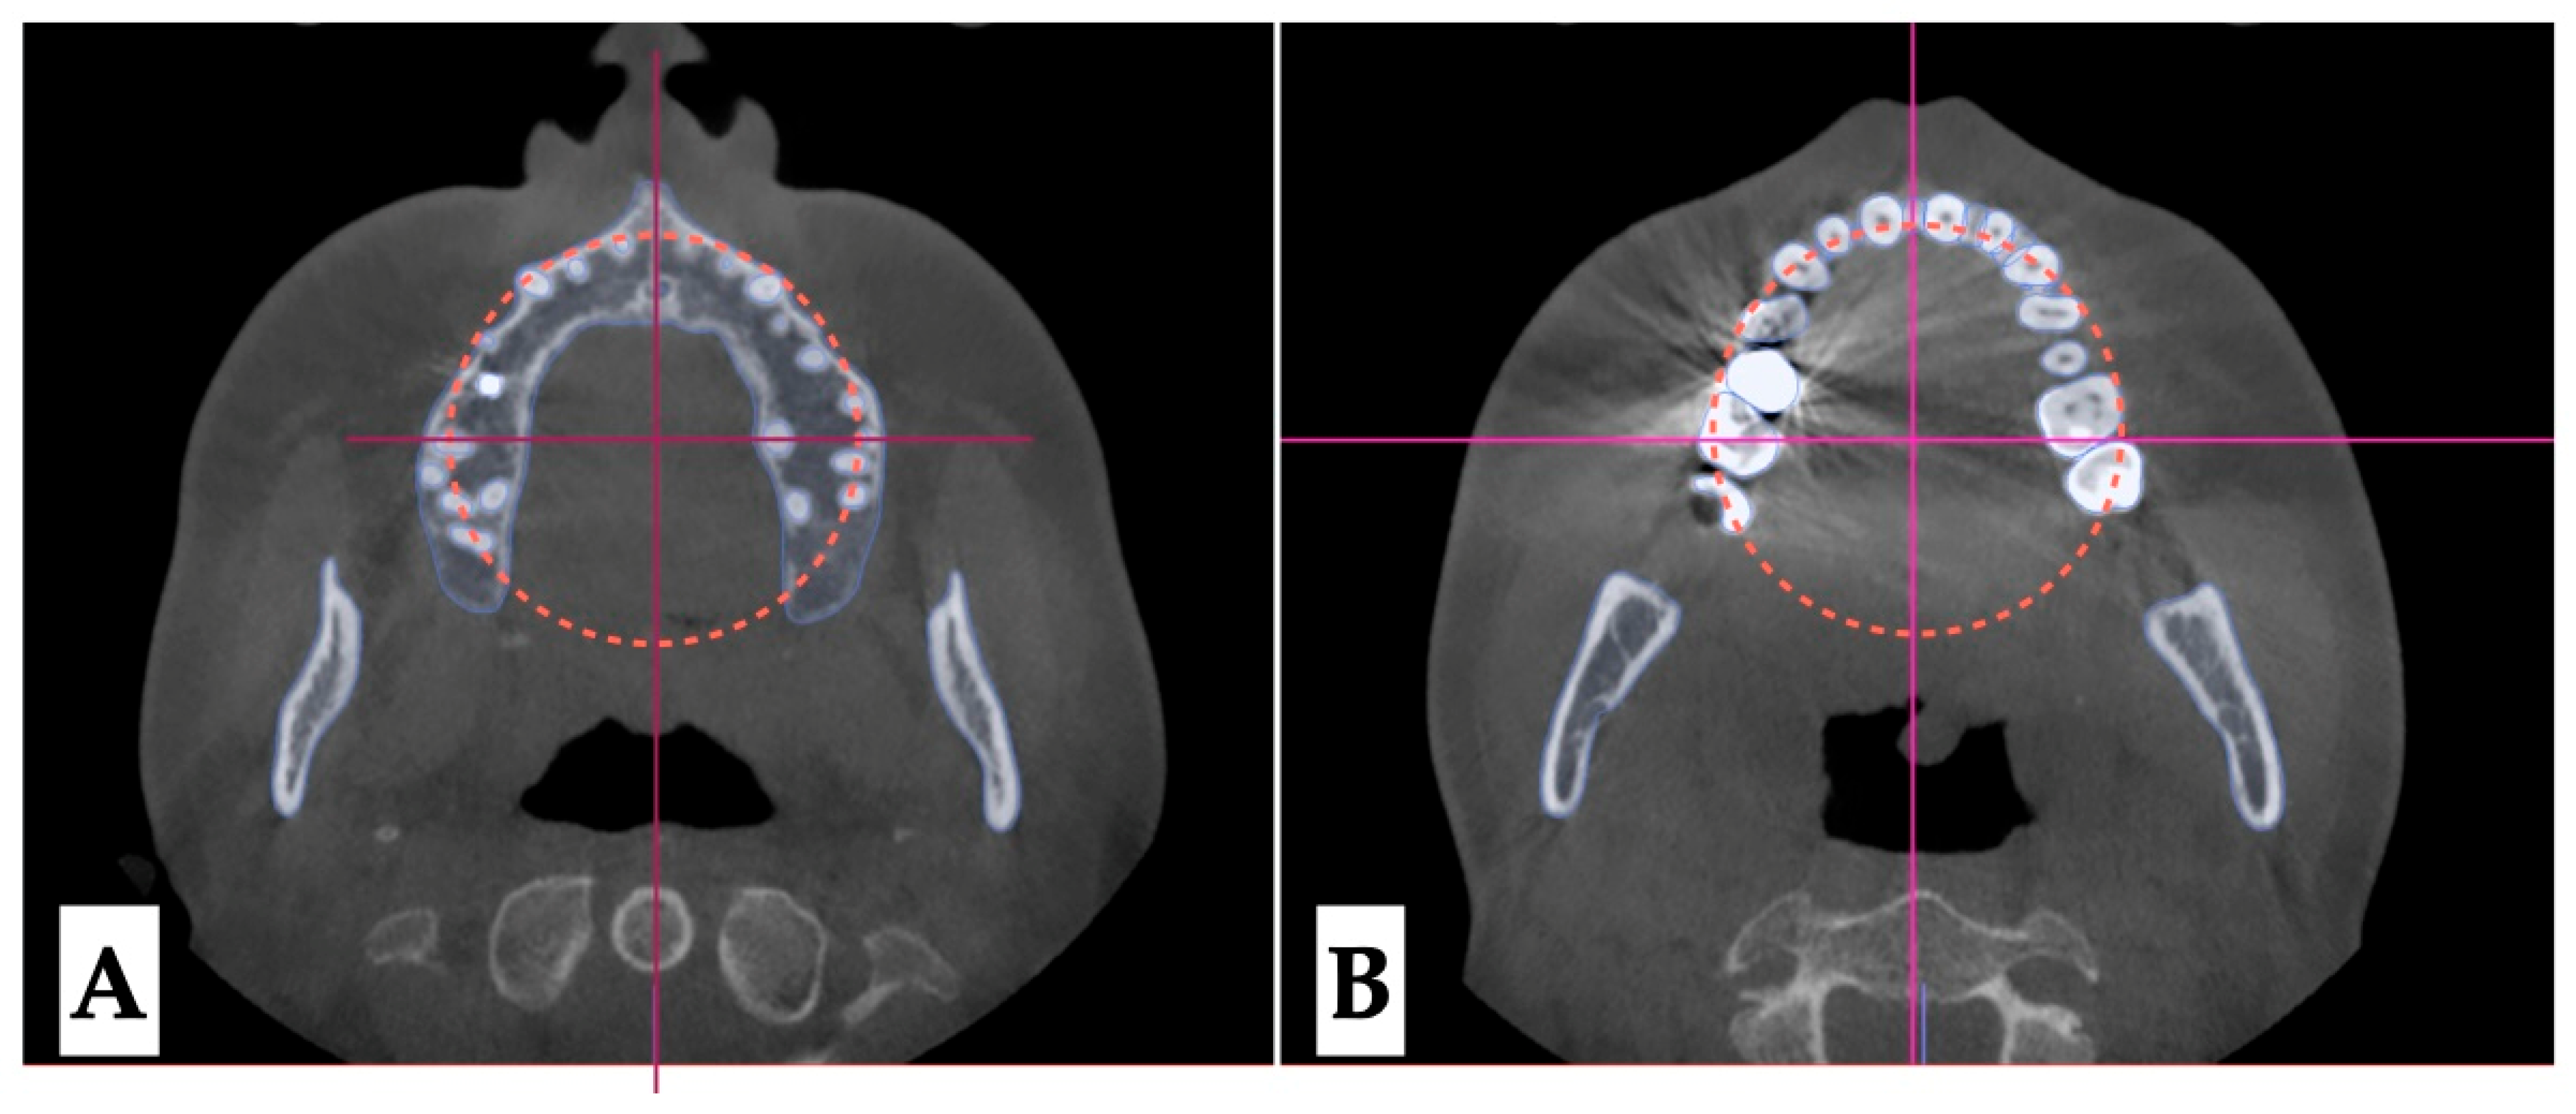

2.3.3. Osteotomy Planning and Appliance Design

2.3.4. Postoperative Assessment, Outcome Analysis, and Asymmetry Correction